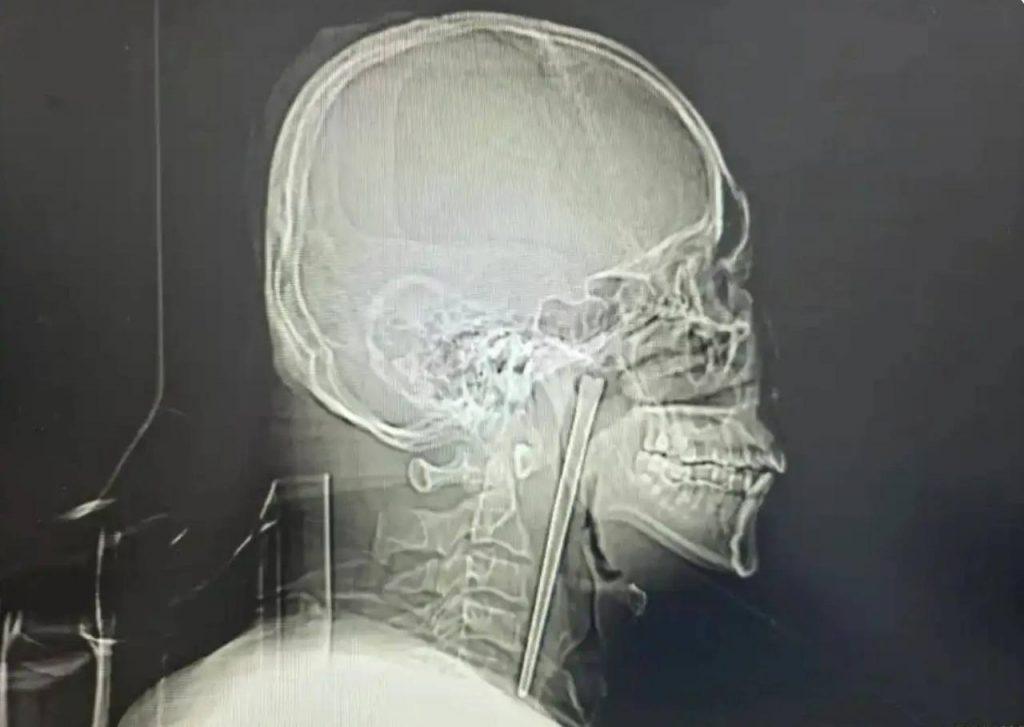

В мире медицины случаются истории, которые кажутся почти невероятными, но они напоминают нам о возможностях человеческого тела и современных технологий. Один из таких случаев произошёл с 46-летним жителем Китая, который восемь лет жил с железной палочкой для еды, застрявшей в его горле. Да, вы не ослышались — целых восемь лет!

История началась, когда мужчина случайно проглотил 12-сантиметровый стержень. Вместо того чтобы обратиться за медицинской помощью, он решил не рисковать — его пугала перспектива операции и хирургического разреза на шее. Всё это время предмет никак не проявлял себя, пока однажды не вызвал острую боль. На этот раз мужчина всё же обратился к врачам, которые успешно извлекли палочку. Сейчас он чувствует себя хорошо и, вероятно, больше не станет игнорировать подобные ситуации.